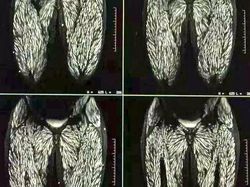

Tubuh dipenuhi parasit akibat konsumsi daging babi mentah selama bertahun-tahun. Kondisi ini dikenal sebagai trikinelosis, penyakit parasit yang disebabkan larva cacing Trichinella dari daging mentah atau setengah matang, yang kemudian berkembang dan membentuk kista di otot. Foto: Boredpanda